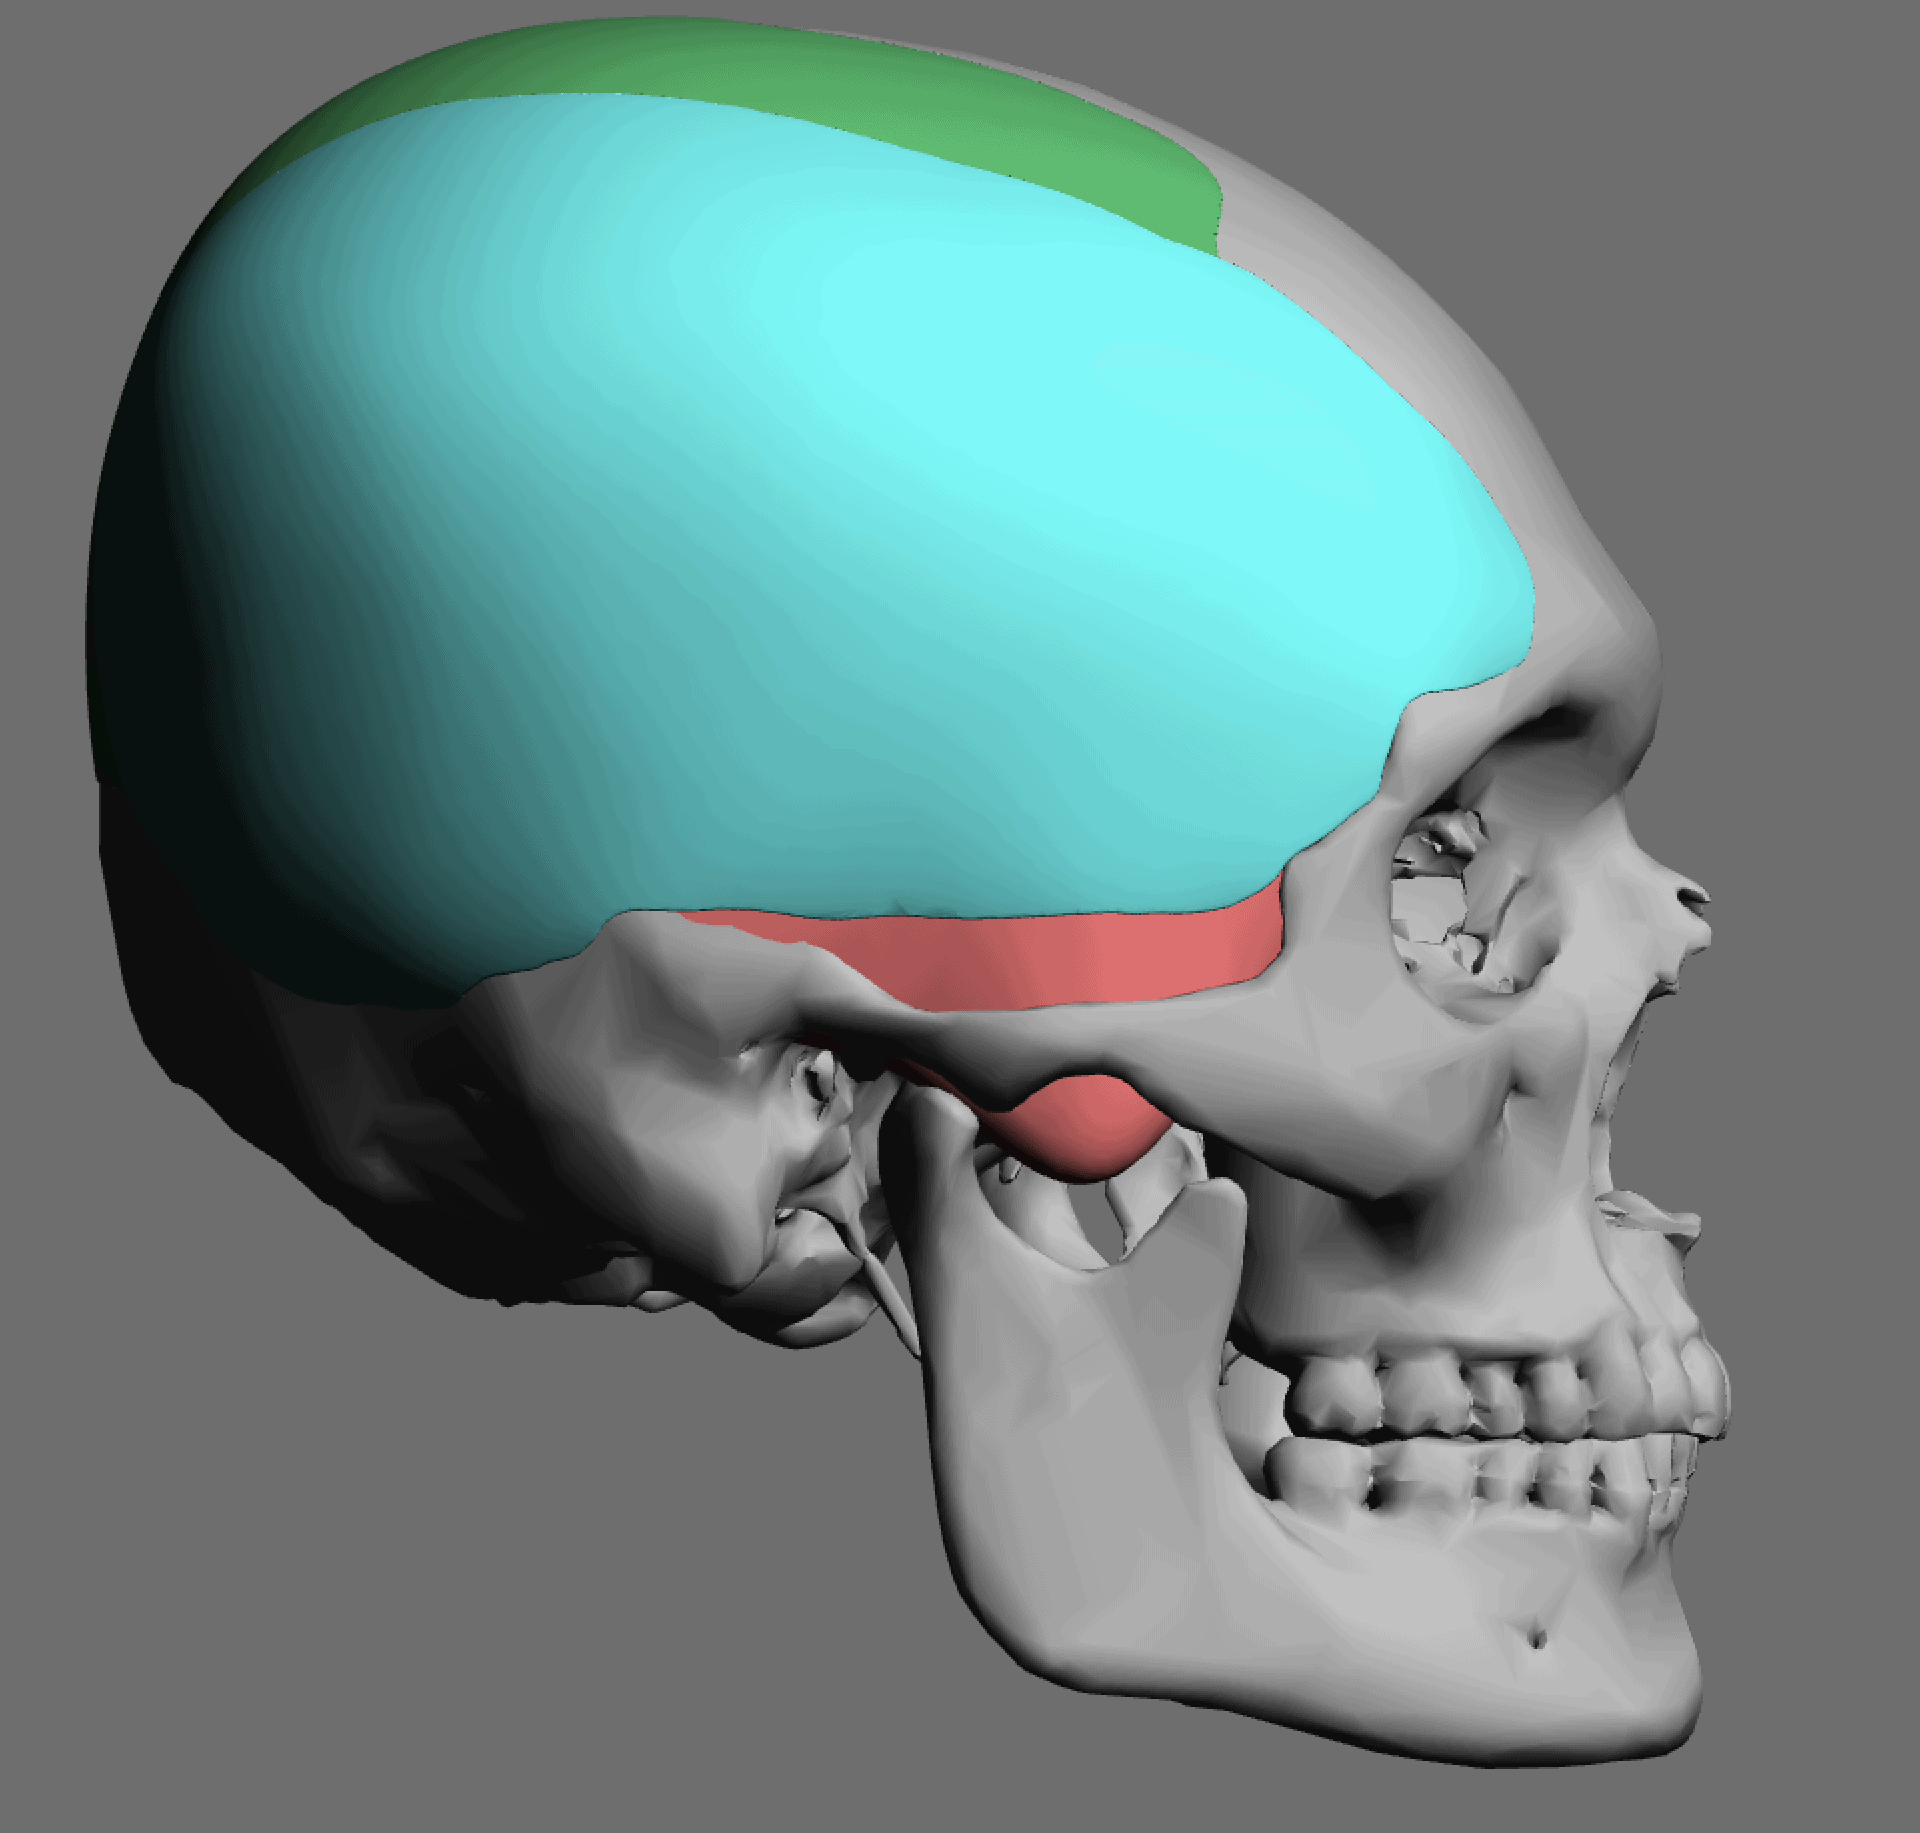

Desire for change of head shape from front view form an inverted V shape to a rounder and wider head shape.

Placement of custom extended forehead-temporal implants through incisions in the crease behind the ear. (he had a prior back of head skull implant which is green in the implant designs and which the head widening implants partially covered it)

Desire for change of head shape from front view form an inverted V shape to a rounder and wider head shape.

Placement of custom extended forehead-temporal implants through incisions in the crease behind the ear. (he had a prior back of head skull implant which is green in the implant designs and which the head widening implants partially covered it)